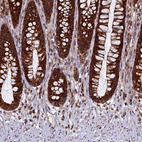

Immunohistochemical staining of human cerebral cortex shows strong positivity in neuropil.